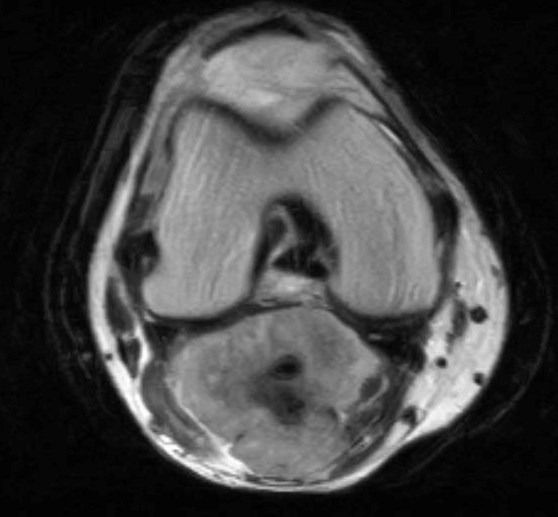

Фото: МРТ остеогенная саркома нижней трети левой бедренной кости

Фото: МРТ коленного сустава. Показано взаимоотношение новообразования с сосудами

Выполнение лишь одного метода визуализации не позволяет достаточно оценить данную патологию, например, рентгенография и компьютерная томография позволяют детально оценить изменение костной ткани, однако из-за специфики оптических свойств не дают полного представления о мягкотканных структурах и распространении по костномозговому каналу, что требует выполнения магнитно-резонансной томографии. Оценить распространение заболевания в целом позволяет применение различных методов радионуклидной диагностики – остеосцинтиграфии, ОФЭКТ и ПЭТ компьютерной томографии.